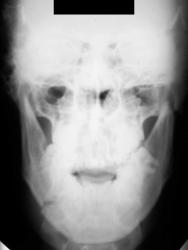

А у нас так ломают челюсти

Выяснение "отношений" продолжается.

Ваше мнение коллеги.